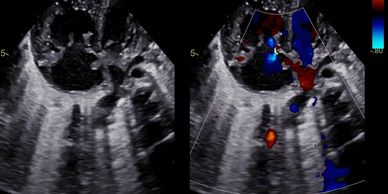

Cas : Tétralogie de Fallot

📚 Cas Cliniques Interactifs — Tétralogie de Fallot Adulte

TOF Cases App · CSC Algeria · Dr. Mohamed Touati Basé sur les recommandations ACC/AHA/HRS/ISACHD/SCAI 2025

Cas Fallot 01

Cas Fallot 02